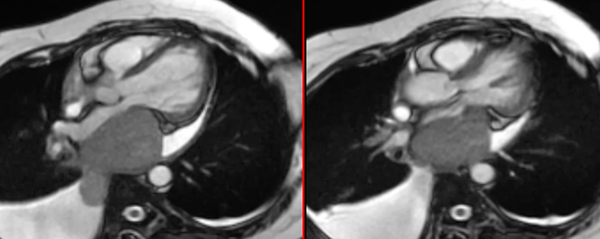

An unusual cause of a double-chambered left ventricle